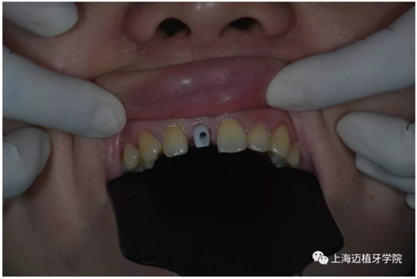

氧化鋯個(gè)性基臺

戴牙前口內(nèi)照片:

口內(nèi)個(gè)性化基臺: